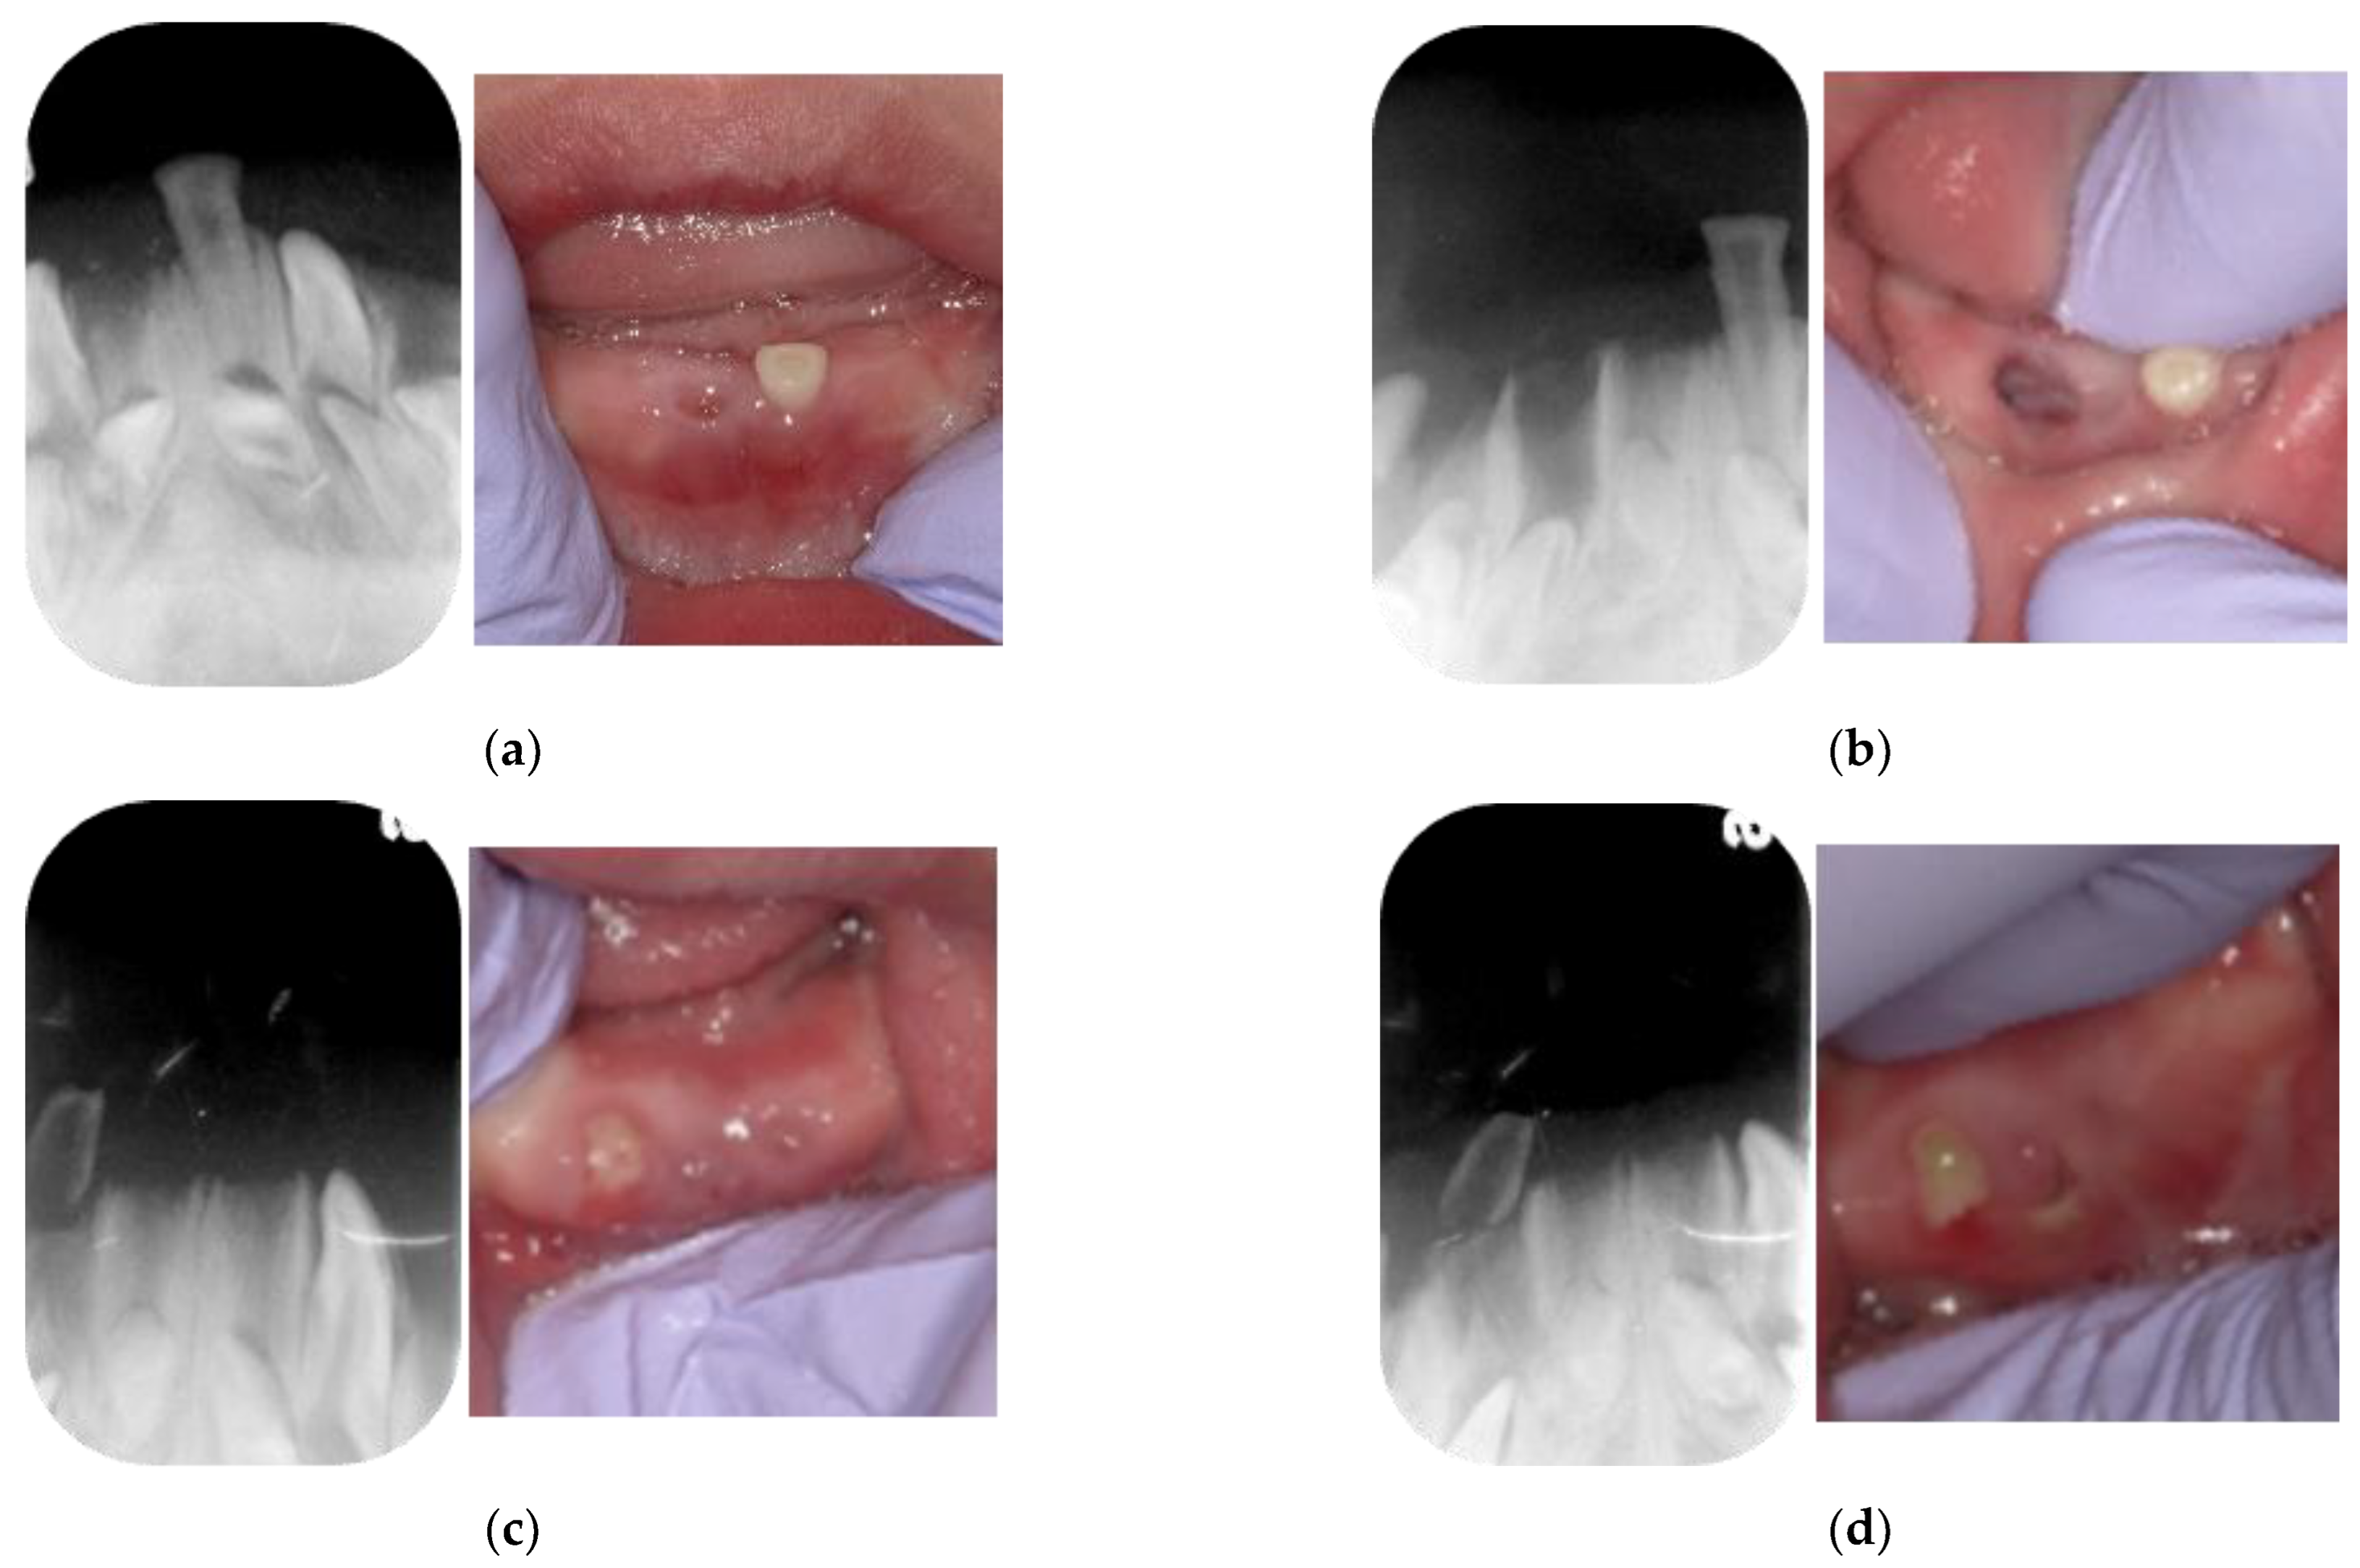

2. Case Presentation